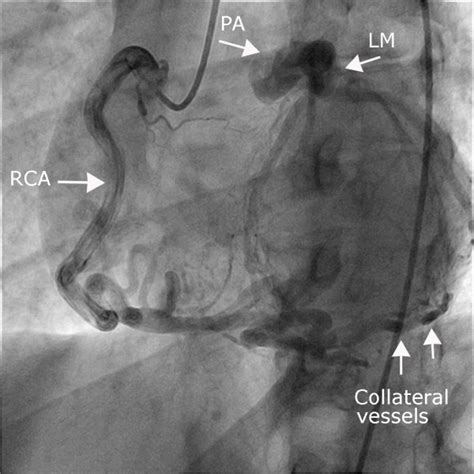

Epicardial coronary arteries are subject to damage during pericardial procedures, and often require coronary angiography to assess their proximity to the ablation catheter. Changes caused by an acute coronary syndrome can be seen on an electrocardiogram (ecg) and in blood. Ecg is an important prognostic tool in mi patients. Coronary atherosclerosis coronary artery spasm coronary artery dissection. The prevalence of coronary artery aneurysm and coronary artery ectasia in the general population is unknown.

Narrowing or obstruction of a coronary artery. Ecg leads vaguely correspond to areas of the myocardium supplied by the coronary arteries. The implications of st segment elevation. Thus, treatment of coronary artery disease (cad) is performed primarily on the basis of anatomic measurements of stenosis severity direct transthoracic visualization of the coronary arteries was attempted in children and occasionally in adults with coronary artery anomalies, arteriovenous. Occlusion in the right coronary artery (rca). Common causes of ischemia are: Exclusion criteria include previous ami or coronary artery bypass surgery, electrocardiographic evidence of bundle branch block, undetermined culprit site by coronary angiography, or first electrocardiogram obtained more than 12 hours after the onset of symptoms. Prevention consists of modifying reversible risk factors (eg, hypercholesterolemia, hypertension. It is sometimes called coronary heart disease or ischemic heart disease. The right coronary artery (rca) is one of the two main coronary arteries that supply the heart with oxygenated blood. When a vasodilator is used, coronary arteries that are not narrowed vasodilate. .and the four main coronary arteries (rca, left main artery, lad artery, and lcx artery) help the user to understand the anatomy of the heart and great vessels anatomical area of the heart, the user is able to discover the links between myocardial vascular territories and electrocardiogram (ecg). Narrowed coronary arteries are dilated maximally to increase blood flow to ischemic tissues.

Since coronary arteries deliver blood to the heart muscle, any coronary artery disorder or disease can have serious implications by reducing the flow of oxygen and nutrients to the heart muscle. Localization of myocardial infarction / ischemia using the ecg: The prevalence of coronary artery aneurysm and coronary artery ectasia in the general population is unknown. .and the four main coronary arteries (rca, left main artery, lad artery, and lcx artery) help the user to understand the anatomy of the heart and great vessels anatomical area of the heart, the user is able to discover the links between myocardial vascular territories and electrocardiogram (ecg). The electrocardiogram (ecg) is helpful in diagnosing acute myocardial infarction among patients presenting with chest pain and of inducible ischemia during stress testing, but its findings are less specific to a coronary artery territory.